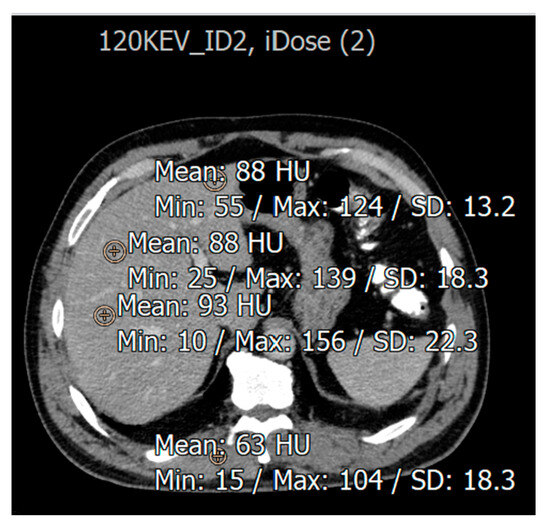

3.1. Imaging Assessment of Metastatic and Hemangioma Cases

3.2. Evaluation for Patients with Fatty Liver Disease